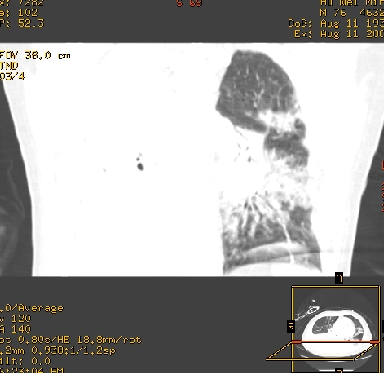

icu病人,几天都没明确诊断。m,76y,咳嗽、咳痰1周,伴气促,右胸痛入院,pe:t38.3c p135 r25 bp135/85。双肺可闻及大量湿罗音,心、腹未见明显异常。诊断:1心衰?2肺部感染?3冠心病?

11号ct

双肺感染性病变,下叶膨胀不全,胸水,左室大。

1)两肺感染性病变(右肺下叶肺脓肿可能)。2)双侧胸腔积液,以右侧为甚。

混合型肺水肿合并感染,肺膨胀不全,胸膜肥厚粘连包裹,同时肺内有陈旧性病灶。注意复查

考虑双肺感染、右肺下叶肺脓肿伴双侧胸腔积液。

ards,肺感染性病变,右下叶实变,双侧胸腔积液,右侧为著,叶间胸膜积液,右上肺陈旧性tb纤维灶,左室大。

考虑双肺感染、右肺下叶肺脓肿伴双侧胸腔积液,肺水肿。

考虑:双肺感染、右肺下叶肺脓肿,双侧胸腔积液,肺水肿.请结合临床.